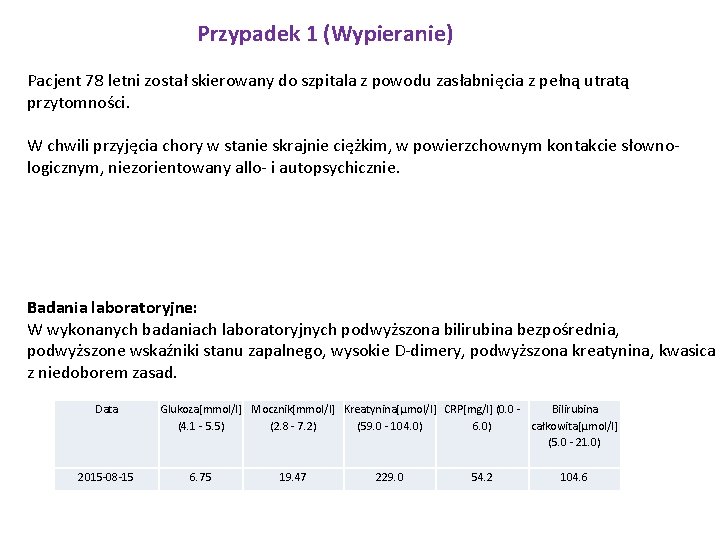

Przypadek 1 (Wypieranie) Pacjent 78 letni został skierowany do szpitala z powodu zasłabnięcia z pełną utratą przytomności. W chwili przyjęcia chory w stanie skrajnie ciężkim, w powierzchownym kontakcie słownologicznym, niezorientowany allo- i autopsychicznie. Badania laboratoryjne: W wykonanych badaniach laboratoryjnych podwyższona bilirubina bezpośrednia, podwyższone wskaźniki stanu zapalnego, wysokie D-dimery, podwyższona kreatynina, kwasica z niedoborem zasad. Data 2015 -08 -15 Glukoza[mmol/l] Mocznik[mmol/l] Kreatynina[µmol/l] CRP[mg/l] (0. 0 - Bilirubina (4. 1 - 5. 5) (2. 8 - 7. 2) (59. 0 - 104. 0) 6. 0) całkowita[µmol/l] (5. 0 - 21. 0) 6. 75 19. 47 229. 0 54. 2 104. 6